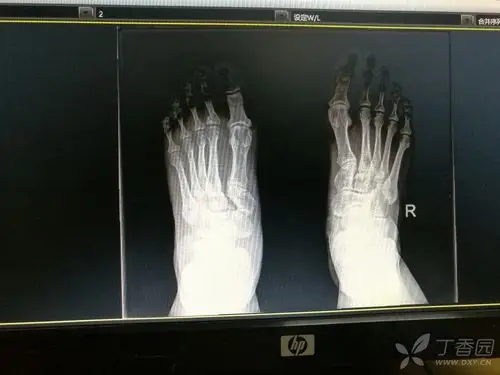

检查提示:脊柱多发爆裂骨折,多处横突骨折,右足舟骨,楔骨粉碎骨折

楔骨骨折

一例楔骨骨折伴脱位,请指导治疗 [病例帖]